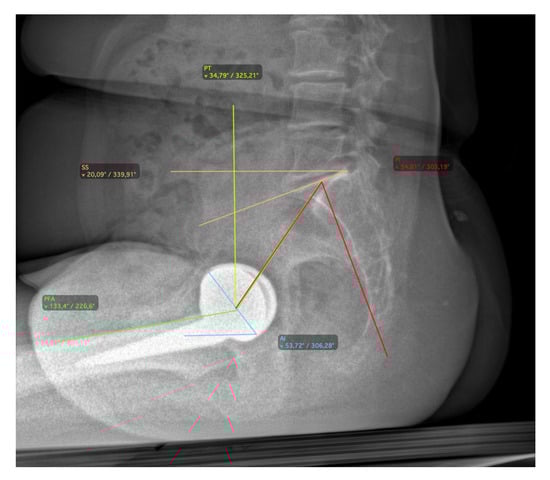

2.2. Radiographic Assessment